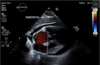

Identify this echocardiography view and level.

A

SAX Mid or Papillary level